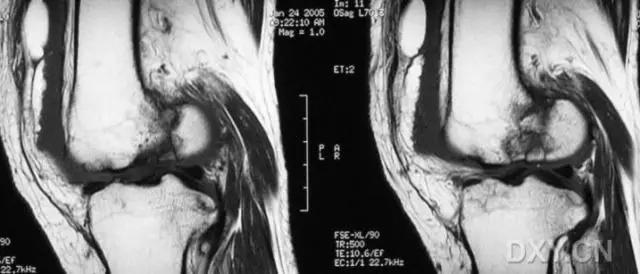

8. Segond 骨折和反向 Segond 骨折

(1)Segond 骨折

是发生在胫骨平台外侧的垂直撕脱性骨折。这种骨折在前后位 X 线片上显示最佳。屈曲位时膝关节受到内旋*力暴**作用,导致皮质骨撕脱性骨折,这种骨折常发生在运动员身上。

常引起股骨内髁和胫骨平台后内侧骨挫伤,75%~100% 的患者伴前交叉韧带断裂,33% 的患者伴外侧半月板损伤。

一位足球运动员的 Segond 骨折。A 正位片示关节线下方胫骨外侧皮质撕脱(箭头)。B MRI 冠状位 T1 加权像示附着于髂胫带的骨折碎片(空箭头)(来源:Radiol Clin N Am 53 (2015) 737–755,YU,Ohio)

(2)反向 Segond 骨折

胫骨平台内侧皮质骨撕脱性骨折,被称为内侧 Segond 骨折或反向 Segond 骨折。这种骨折的旋转机制与 Segond 骨折相反,该骨折与后交叉韧带断裂及内侧半月板损伤相关。

一位足球运动员的反向 Segond 骨折。A 正位片示关节线处的胫骨内侧见一细小骨折片(箭头)。B MRI 冠状位 T1 加权像示骨折片出现在内侧副韧带关节囊附着处(方框)(来源:Radiol Clin N Am 53 (2015) 737–755,YU,Ohio)